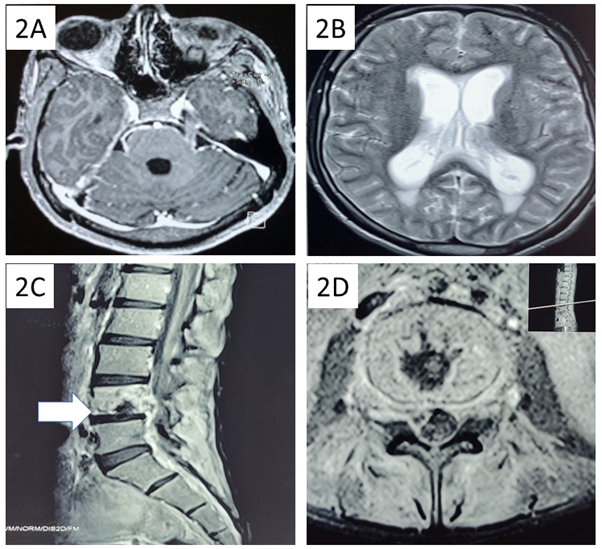

His initial laboratory data normal complete blood count, but elevated alanine transaminase 74 U/L (10-40 U/L), aspartate transaminase 45 (10-40 U/L), and creatine kinase 493 U/L (24-195 U/L). Serology for hepatitis B, C, and human immunodeficiency virus (HIV) were negative. Cerebrospinal fluid (CSF) showed a raised pressure of 40 cm of water, cell count 280 cells/µL (Neutrophils-15%, Lymphocytes- 85%), protein 149 mg/dL, glucose 12 mg/dL (corresponding blood sugar 98 mg/dL) and no bacterial or fungal growth. CSF cartridge-based nucleic acid amplification test (CBNAAT) and viral panel reports came negative. Serum immunoglobulin M leptospira titer was 26.4 Units (<9 units). His blood polymerase chain reaction (PCR) was also positive for leptospira. By day 9, there was an improvement in sensorium. However, the fever did not subside despite 2 weeks of doxycycline therapy. He also started complaining of low back ache with tenderness over lumbar spine. Contrast-enhanced computed tomography (CECT) thorax, abdomen and pelvis was suggestive of disseminated tuberculosis (Fig. 1).

Fig. 1: Contrast enhanced computed tomography of chest and abdomen revealing multiple centrilobular nodules in upper lobe of left lung parenchyma (1A) and multiple enlarged mediastinal, bilateral hilar and intraabdominal (arrow) lymph nodes (1B) suggestive of disseminated tuberculosis.